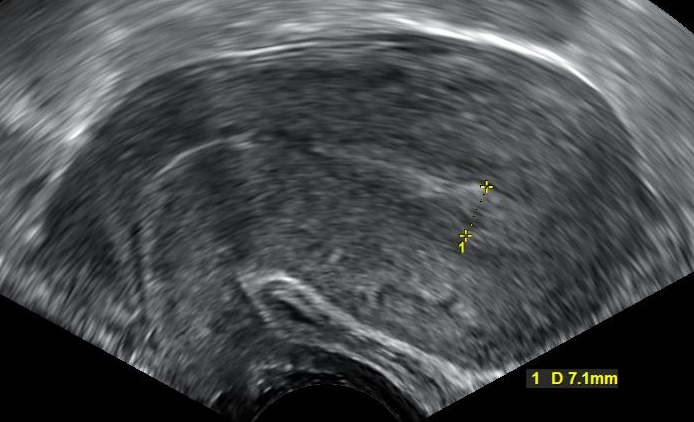

Blood clot: Blood clots are uniform red blood clumps. An ultrasound scan shows them as black areas.

Miscarriage: During miscarriage grayish tissue parts are discharged, together with blood clots. An ultrasound scan shows the products of conception as white areas.

- Ultrasound scan shows blood clots as black areas, and the products of conception – as white areas.